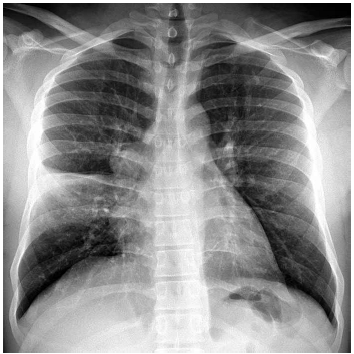

Homem de 73 anos de idade procura assistência médica com o relato de febre, dispneia e expectoração amarelada há 3 dias. Não há comorbidades, etilismo, tabagismo, vômitos ou diarreia. O paciente tomou as duas doses da vacina da Pfizer para COVID-19 há mais de 1 mês. Ao exame físico: consciente, orientado, corado e anictérico; PA: 125 x 82 mmHg, FC: 95 bpm, T: 38,1 ºC, FR: 20 ipm e SatO2: 97%; cardiopulmonar: NDN; extremidades bem perfundidas, sem edema. A radiografia realizada é mostrada a seguir:

Admitindo-se que os exames laboratoriais estão dentro dos limites da normalidade, a conduta de escolha é prescrever